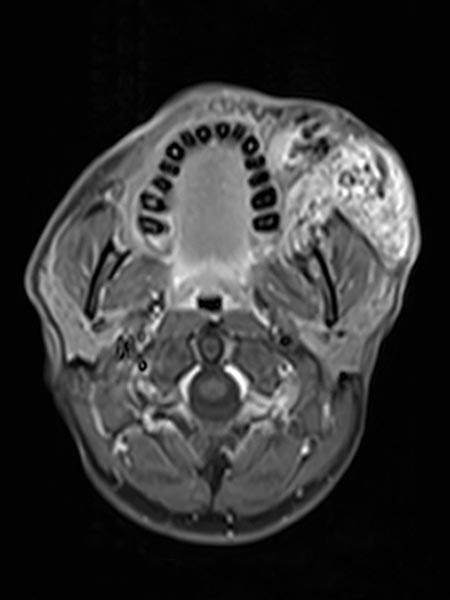

Axiale, T2-gewichtete MRT auf Höhe der Wange zeigt die AVM relativ hyperintens mit Ödem des Gewebes und Ausdehnung bis zum linken Unterkiefer. Im rostralen Abschnitt auch einige schwarze flow-voids durch stark durchblutete Arterien innerhalb der AVM.

Inhomogenes, vor allem peripheres Enhancement der proliferierenden AVM in dieser axialen fettunterdrückten T1-gewichteten MRT nach Kontrastmittelgabe. Keine abgrenzbare, eigentlich solide Komponente, anders als bei einem echten vaskulären Tumor.